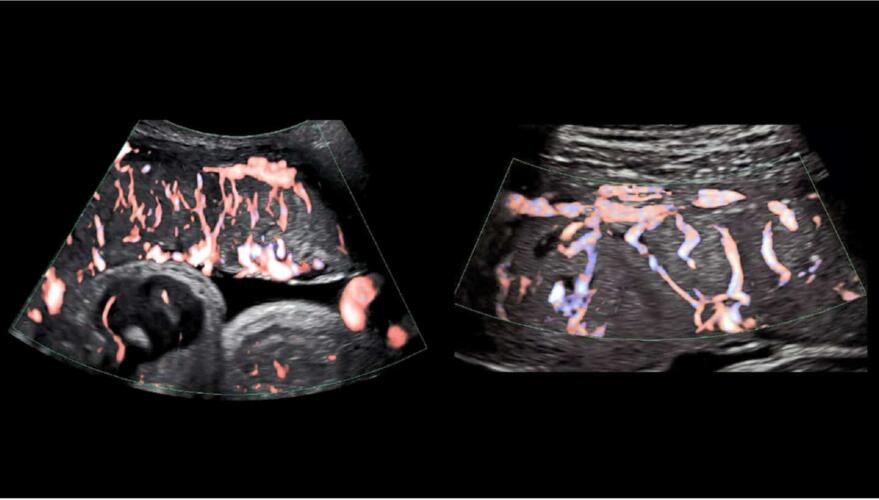

ولكن بخلاف المعلومات الأساسية عنها، لا يعرف الخبراء سوى القليل جداً عن كيفية تطور المشيمة وعملها. في منشور حديث على المدونة، تقول ديانا بيانكي كبيرة الباحثين في المعهد الوطني للصحة (NIH): «المشيمة هي أقل الأعضاء المفهومة والمدروسة». ثم تشرح كيف يمكن لتطوير تقنيات أفضل للتصوير بالموجات فوق الصوتية والتصوير بالرنين المغناطيسي أن تساعد الأطباء على دراسة المشيمة أثناء الحمل، وهي التقنيات التي استخدمتها كلية الطب في شرق فيرجينيا وفرع الطب بجامعة تكساس لدراسة الأوعية الدموية المشيمية، كما هو موضح أعلاه.